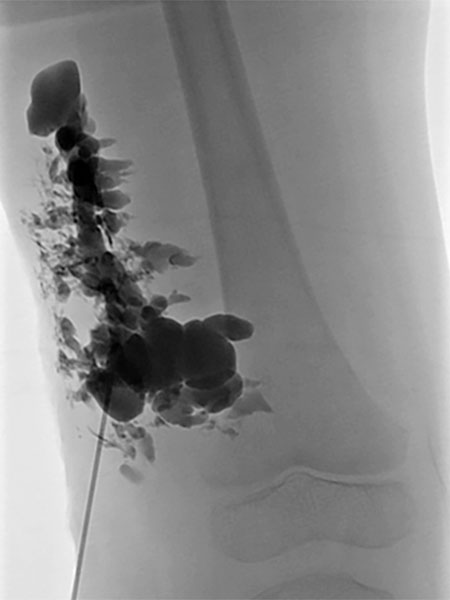

Lymphography with contrast injection directly into the lymphatic malformation subcutaneously, underneath the capillary malformation laterally on the thigh which is visible on the skin. The entire lymphatic malformation is contrasted from this needle position. Thus the ideal position for sclerosing this portion.

Re-puncture and lymphography with contrast injection will contrast additional parts of the lymphatic malformation, which can then be sclerosed.

Injection of sclerosant (in this case picibanil = OK-432), which is in itself non-contrasting, displaces the previously injected contrast. In this way, the entire lymphatic malformation is sclerosed in successive steps. This results in sealing of the skin and decreases future lymphorrhea. The marginal vein is additionally occluded by radiofrequency ablation (not shown) to prevent thromboembolism.